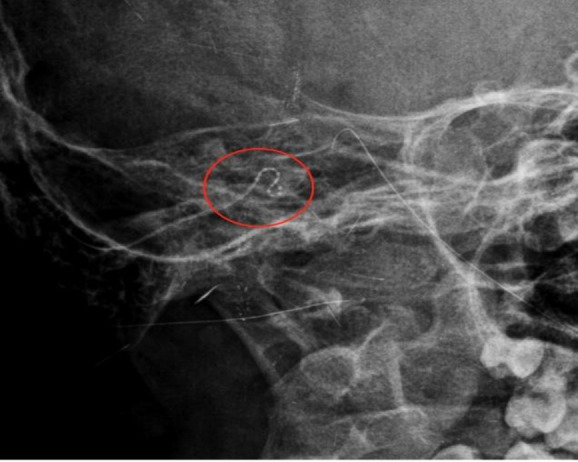

Results: Thirty-three (29 children, 4 adults) of 720 patients (871 CI) at our clinic required revision surgery, representing a revision surgery rate of 4.58%. The most common reason for revision was device failure (10 patients), followed by skin and electrode problems, with electrode tip fold-over in 6 patients, a broken electrode cable in 1 patient, skin flap complications in 6 patients, displacement of the magnet in 1 patient, cholesteatoma in 1 patient, electrode migration in 6 patients, misplacement of the electrode array into the internal acoustic canal in 1 patient, and explantation of the electrode cable in the external auditory canal in 1 patient. We had only one major complication after revision surgery.

Conclusion: We recommend performing routine postoperative imaging, even if intraoperative telemetries are normal, to diagnose electrode misplacement or electrode tip fold-over. Additionally, we recommend long-term regular follow-up of children, in particular, because our study showed that the number of revision surgeries was higher in children who received implants at an early age.